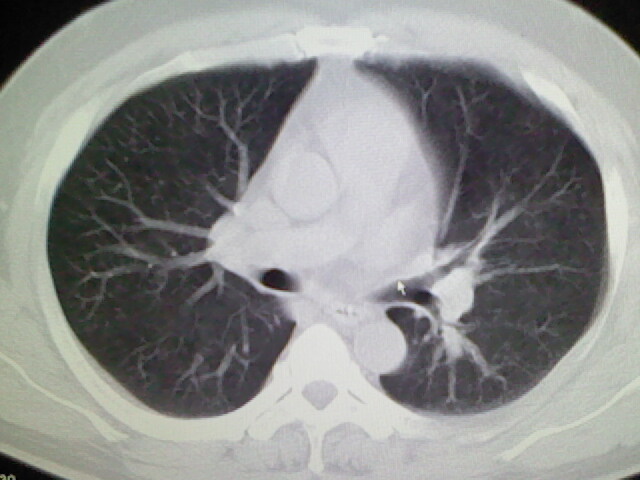

标题: CT17932:临床怀疑肺栓塞

男,34岁,自觉右侧胸痹,胸闷3天余

两肺纹理增多,余未见明确异常。

右侧肺动脉似见密度稍低影,请在机器的薄层上再看看有没有充盈缺损。